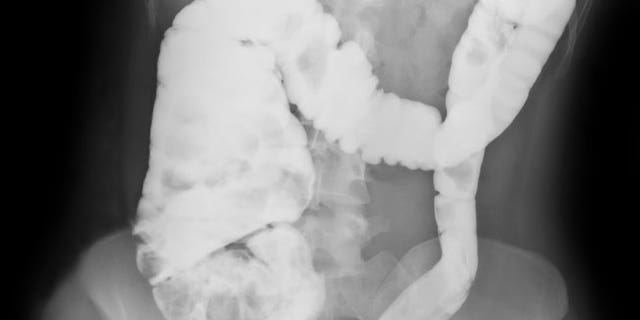

In humans, fibrosis occurs as a response to chronic inflammation; it is a common side effect of conditions such as liver cirrhosis, kidney disease, and heart attacks. (It also occurs, to a lesser extent, during normal aging.) For patients with Crohn’s disease—a type of inflammatory bowel disease—surgery is often needed to remove or repair parts of the intestines that have been damaged by fibrosis.

For the study, published in the journal Science Immunology, the researchers infected lab mice with a type of salmonella that mimics the symptoms of Crohn’s disease. They found that mice with a specific genetic mutation did not develop fibrosis, while the rest did.